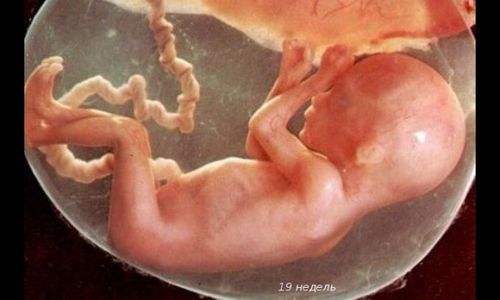

На цей тиждень припадає зазвичай перше УЗД вагітної. Статеві органи малюка вже помітні, і лікар в 95% випадком може сказати вам стать дитини.

Його довжина - 10 см. Він важить близько 70 г, як крихітний кошеня при народженні.

Можна добре розглянути личко малюка. Як думаєте, він схожий на тата? Дитина активно моргає, відкриває ротик і удосконалює хапальний рефлекс.